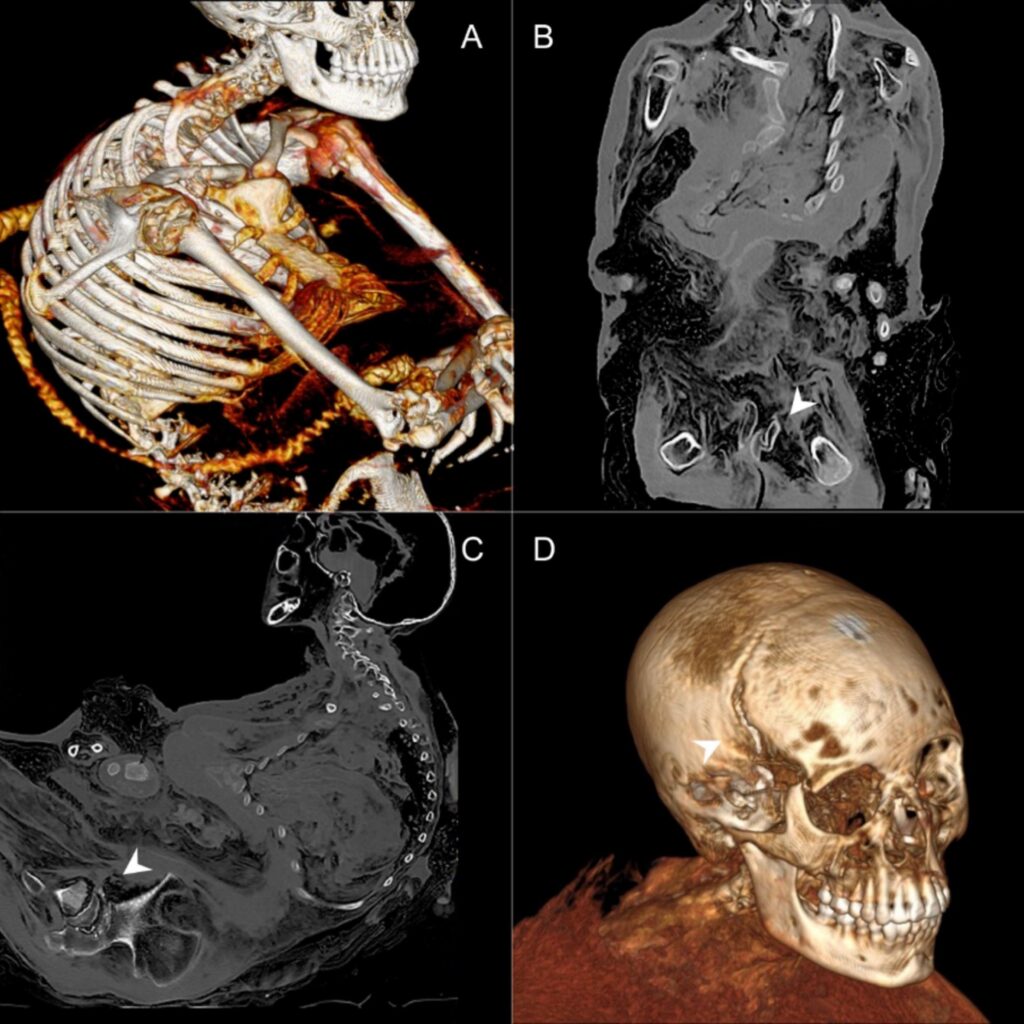

– „Dama z Ampato” była badana tomografem w USA, ale miało to miejsce rok po jej znalezieniu, czyli w 1996 r. Rozdzielczość tomografu wtedy była dużo słabsza. Widać było np. pęknięcie kości czaszki, ale narządów wewnętrznych już nie. Tamte badania nie były zresztą nigdy publikowane naukowo. Dlatego nasze badanie tomografem to zupełne coś nowego – podkreśla dr Socha.

– W każdej z tych mumii odkryliśmy coś nowego. W przypadku Ampato 1, czyli „Damy z Ampato”, potwierdziliśmy pęknięcia czaszki na skutek uderzenia. Przekonaliśmy się, że nie tylko pęknięta jest głowa na zbiegu szwów, ale także przesunięta cała kość czołowa, złamany nos i kości oczodołów – wyjaśnia bioarcheolog.

– Mumia „Damy” została znaleziona na stoku, wypadła z grobu po tym jak się zapadł. Można więc było się zastanawiać, czy uszkodzenia powstały właśnie wtedy. Jednak w kryminologii i medycynie określa się ten typ złamania jako „złamanie zielonej gałązki”. Kości dzieci są jeszcze dosyć elastyczne, nie tak kruche i pozbawione kolagenu jak u osób starszych. Złamanie u dziecka wygląda więc jak złamanie gałązki, która się nie kruszy, tylko jak gdyby rozwarstwia. Dzięki temu mogliśmy stwierdzić, że uszkodzenie nosa miało miejsce za życia dziecka, a uraz głowy był przyczyną śmierci – opowiada badaczka.

Analizy wykazały, że cała czwórka dzieci zginęła w wyniku uderzenia w głowę. U jednej z ofiar, ośmioletniej dziewczynki – Ampato 2 – stwierdzono krwiak śródmózgowy. Ponadto widoczne było u niej nienaturalne dla dziecka w tym wieku poszerzenie przełyku i liczne zwapnienia w płucach. Razem objawy te tworzą obraz charakterystyczny dla choroby Chagasa, pasożytniczego schorzenia, które bardzo często występuje w tym regionie. Bez badań genetycznych nie można tego jednoznacznie potwierdzić, ale jest to bardzo prawdopodobne.

– U „Damy z Ampato” znaleźliśmy też urazy klatki piersiowej i w obrębie miednicy oraz, także w miednicy, dużo skupień zamarzniętej krwi. Dziewczynka została zabita na szczycie góry, ze złamaną miednicą by tam nie weszła. Prawdopodobnie zabito ją lub ogłuszono uderzeniem w głowę, a następnie związano ciasno tekstyliami. To mogło doprowadzić do przesunięcia kości obojczyków, zapadnięcia klatki piersiowej i złamań miednicy – mówi dr Dagmara Socha.

Największą niespodzianką była mumia Ampato 4. Okazało się, że jej kości są przemieszane, ma bardzo dużą dziurę na plecach, a część kręgosłupa jak gdyby wpadła do środka jamy brzusznej. Przemieszanie kości wskazuje na powtórny pochówek. Ponadto do wewnątrz włożone były tekstylia i kilka kamieni, co świadczyłoby o celowej mumifikacji.